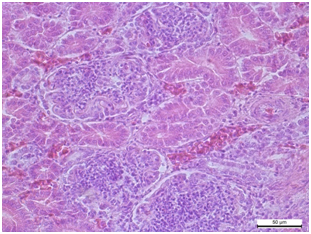

При стафілококової септицемії характерними є некрози та судинні розлади у багатьох паренхіматозних органах, включаючи печінку, селезінку, нирки і легені.

Рис. 2. Печінка. Розширення та переповнення кров’ю синусоїдних капілярів, центральної вени та скупчення колоній мікроорганізмів. Гематоксилін та еозин. х 400